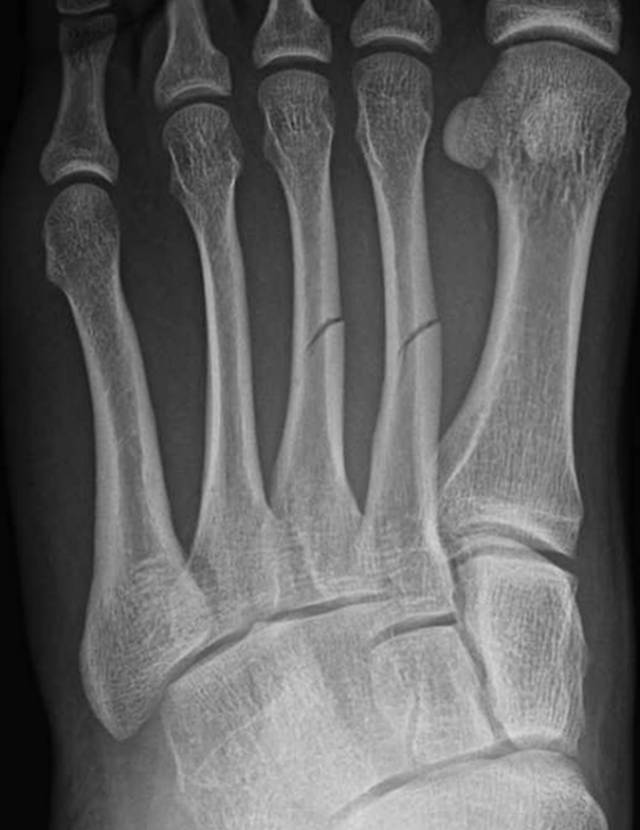

当骨折存在时,在X光片上看到它的最佳机会是多个视图被正确定位并且技术上足够。对于数字放射线照相,不足的管电流(毫安)将导致曝光不足的X光片,其具有比正常曝光的X射线照片少的信息。因为显示设置可以呈现具有期望的灰度级,对比度和亮度的图像,所以X线照片看起来可能会被正确曝光。我们提出一个例子,其中骨折在正确定位和暴露的X光片上是明显的,但在几天后获得的不适当定位和曝光不足的随访X线片上不明显(图2)。

图2A-19岁男性运动损伤后。A,初始斜位放射照片显示不完全的第二和第三跖骨轴骨折。

图 2B-19岁男性运动损伤后。B,1周后在没有放射技术人员的门诊办公室获得的随访X光照片不显示跖骨骨折,因为穿透不足和不正确的管成角。注意缺乏小梁骨细节和跖骨和导管骨关节的可视性差。